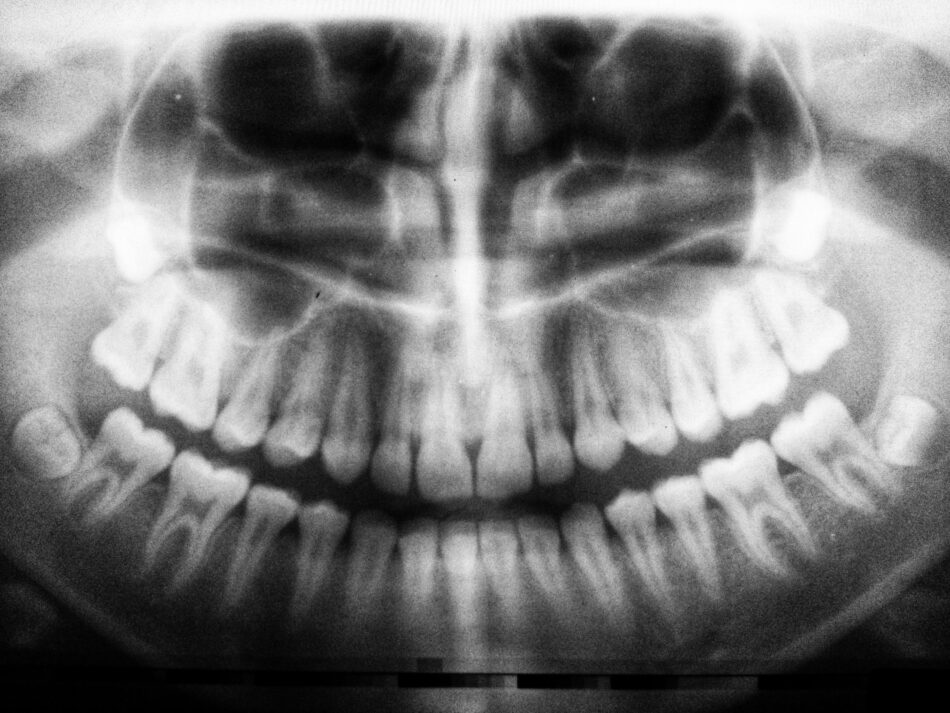

Dental health plays an essential role in overall well-being, and one of the most useful diagnostic tools in dentistry is the panoramic dental X-ray. Unlike standard X-rays, this technique provides a full view of the upper and lower jaws, teeth, temporomandibular joints, and surrounding bone structure in a single image. Because it offers such a comprehensive picture, many dentists recommend it as an early step in assessing oral health. However, one aspect that patients often overlook is the importance of checking the Panoramic Dental X-Ray Cost in Dubai before moving forward with their treatment.

Panoramic dental X-rays are often recommended for preventive care. They reveal potential issues such as impacted teeth, cysts, jawbone irregularities, or early signs of oral disease. Addressing these problems at an early stage can save patients from complex procedures later. Understanding the expected cost in advance allows individuals to integrate preventive diagnostics into their oral health routine without hesitation or delay.